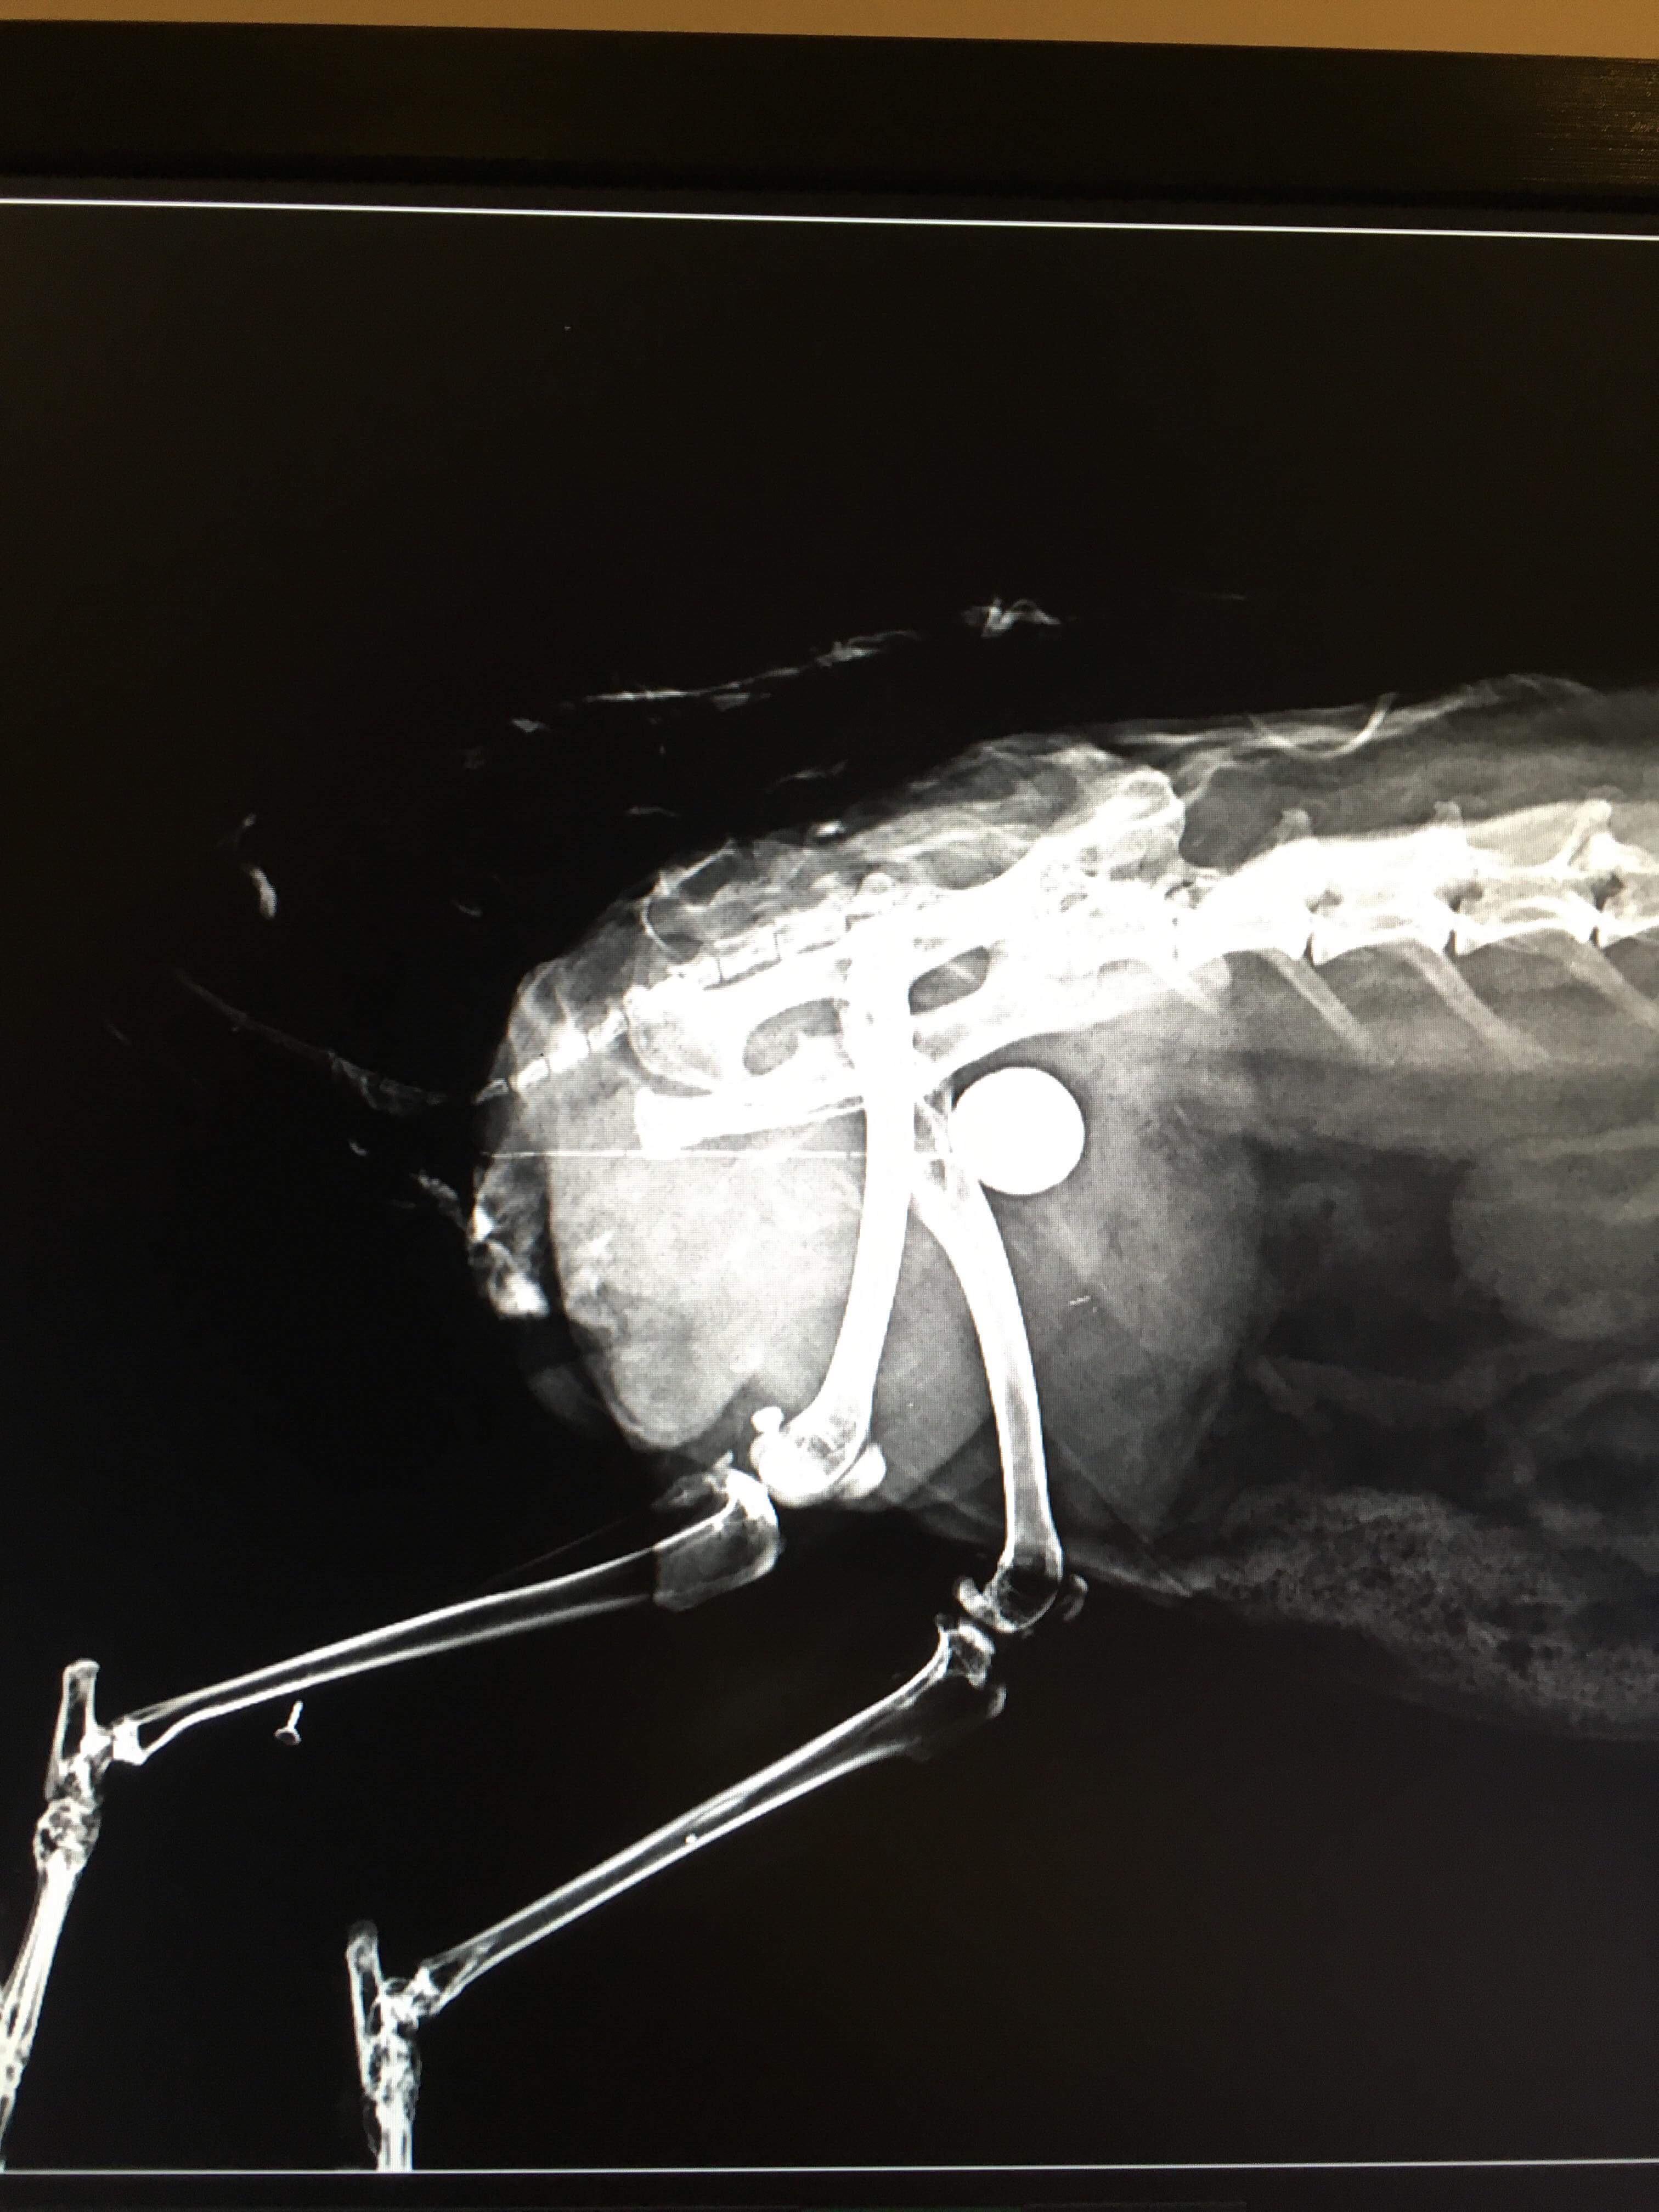

Xray of my rabbit's bladder stone (additional info in comments) r/VetTech Rabbit Bladder Stone Surgery Cost Learn about urolithiasis, urinary sludge, and stones in rabbits. These problems range from irritating sludge in the bladder, to kidney problems, to the formation. Explore causes, symptoms, and treatment options to ensure your rabbit's urinary health. Has anyone had a rabbit undergo this. I can verify with our pig, that her bladder stones and bladder sludge surgery and meds combo. Rabbit Bladder Stone Surgery Cost.

Urolithiasis bladder stone lateral radiograph in Rabbits (Lapis Rabbit Bladder Stone Surgery Cost Learn about urolithiasis, urinary sludge, and stones in rabbits. Explore causes, symptoms, and treatment options to ensure your rabbit's urinary health. I can verify with our pig, that her bladder stones and bladder sludge surgery and meds combo cost over $2,000 over about a month. These problems range from irritating sludge in the bladder, to kidney problems, to the formation.. Rabbit Bladder Stone Surgery Cost.